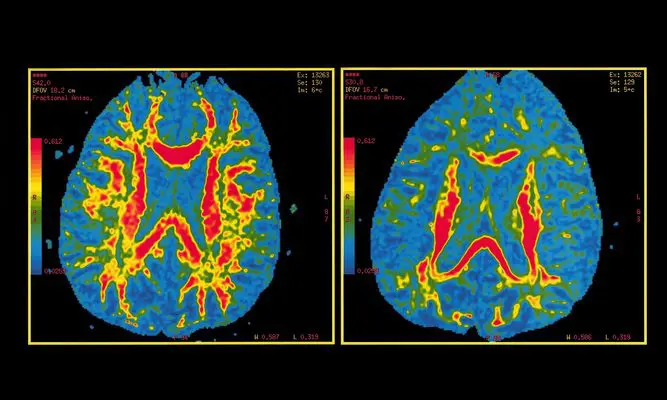

Los autores constataron que el puntaje de PHS era un «fuerte» predictor de la edad de inicio de la enfermedad y la progresión del envejecimiento normal con la enfermedad de Alzheimer, y el deterioro cerebral y cognitivo asociado a ella.